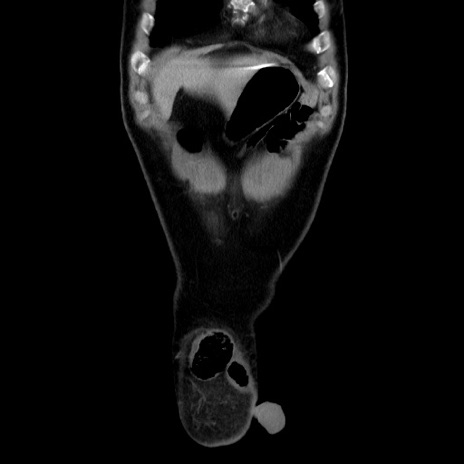

矢状断像